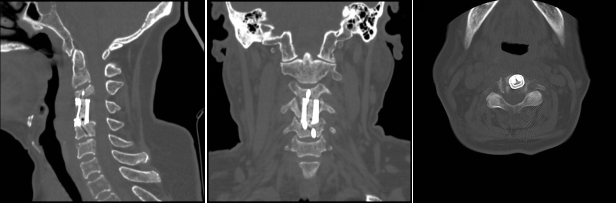

術(shù)后影像學(xué)顯示,植入內(nèi)植物位置滿意,與終板匹配性良好,穩(wěn)定性佳。術(shù)后患者生命體征平穩(wěn),癥狀明顯緩解,活動(dòng)良好,目前已出院。

術(shù)前影像:C3、4椎體病變,椎管狹窄